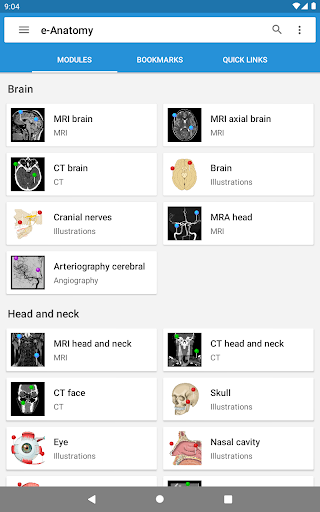

IMAIOS e-Anatomy es un atlas de anatomía humana para médicos, radiólogos, estudiantes de medicina y técnicos en radiología. Echa un vistazo a más de 26 000 imágenes médicas y anatómicas de forma gratuita antes de suscribirte a nuestro detallado atlas de anatomía humana.

e-Anatomy se basa en el galardonado atlas en línea IMAIOS e-Anatomy. Lleva contigo la referencia más completa de anatomía humana, dondequiera que vayas, en tu dispositivo móvil o tableta.

e-Anatomy tiene más de 26 000 imágenes que contienen series de imágenes en vistas axiales, coronales y sagitales, así como radiografías, angiografías, imágenes de disección, gráficos anatómicos e ilustraciones. Todas las imágenes médicas fueron etiquetadas cuidadosamente, más de 967 000 etiquetas disponibles en 12 idiomas, incluida la Terminologia Anatomica latina.

Nuevo: ahora puede filtrar los módulos por región o por tipo de contenido para que pueda encontrar el módulo que busca mucho más rápido.

- Dos nuevos módulos: cerebro - TOF y angiografía cerebral, atlas de la anatomía neurovascular normal de las arterias del cerebro en una angiogafia cerebral. -La interfaz ha sido rediseñada. -Una nueva pestaña llamada "QuickLinks" está disponible, enviando módulos en secciones del cuerpo humano y permitiéndole viajar rápidamente a los módulos que está buscando. -Corregidos pequeños errores.